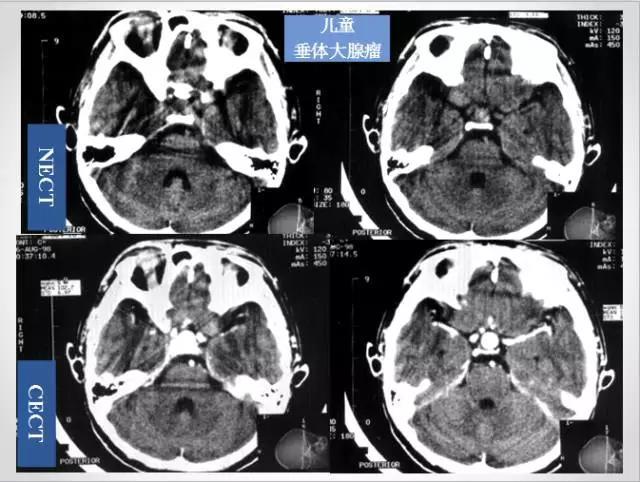

十分钟学会头部CT解剖(多图)

作为一准备毕业的实习生,收集了不少的资料,头颅CT一直是我比较头痛的,现将资料上传,与各位、特别是与我一样是实习生的同行们分享。